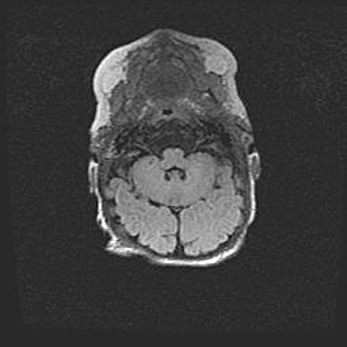

Открытая гидроцефалия.

Возраст: 6 месяцев 15 дней

Вес: 6200 г

Пол: женский

Окружность головы: 41 см

Срок гестации: 38 недель

Гидроцефалия головного мозга у новорожденных – это скопление избыточного количества цереброспинальной жидкости в головном мозге. Ее избыточное скопление в мозге приводит к патологическому расширению желудочков мозга (четырех полостей, расположенных в глубине белого вещества мозга, заполненных цереброспинальной жидкостью и связанных узкими проходами).

Открытый тип гидроцефалии (сообщающаяся) наблюдается тогда, когда нарушен механизм всасывания ликвора в системный кровоток. При этом типе причиной заболевания чаще всего является перенесенные ранее инфекции (например: менингит),  либо же наличие крови в субарахноидальном пространстве.